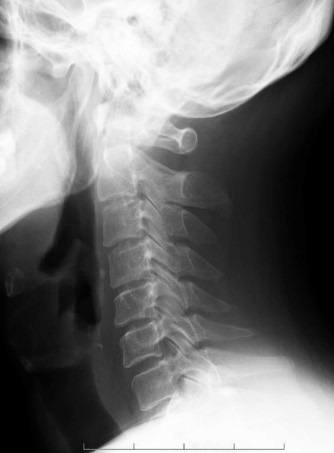

Загальна рентгенографія

Спеціальні можливості для рентгенографії:

• Вертиграфна стійка,

Переміщення по-висоті – близько 1,2 м,

Вбудована решітка,

• 2-га рентгенівська трубка в стельовому кріпленні:

Повздовжнє переміщення – більше 4 м,

Поперечне переміщення – більше 2 м,

Переміщення по-висоті – близько 1,7 м,

Зміна фокусної відстані 850..2550 мм;

• Плоский детектор Pixum 35×43EZ (бездротовий).